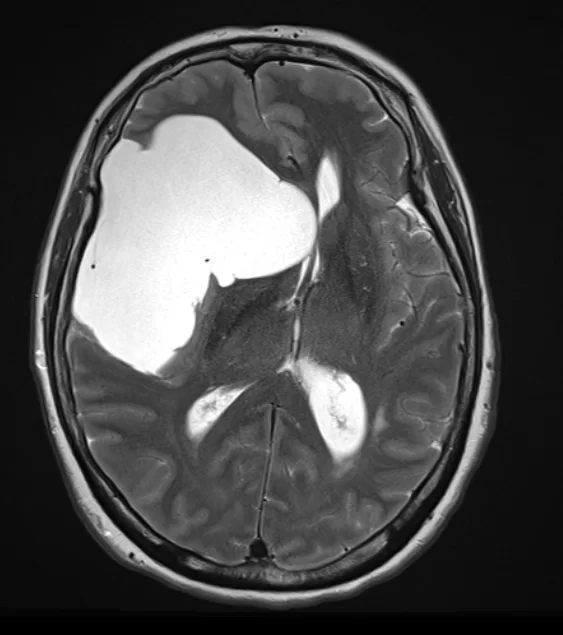

Αραχνοειδής Κύστη Εγκεφάλου

Ασθενής γυναίκα 58 ετών με πονοκεφάλους και διαταραχές όρασης. Ο οφθαλμολογικός έλεγχος έδειξε οίδημα οπτικών θηλών άμφω και σημαντικό περιορισμό των οπτικών πεδίων. Τα συμπτώματα